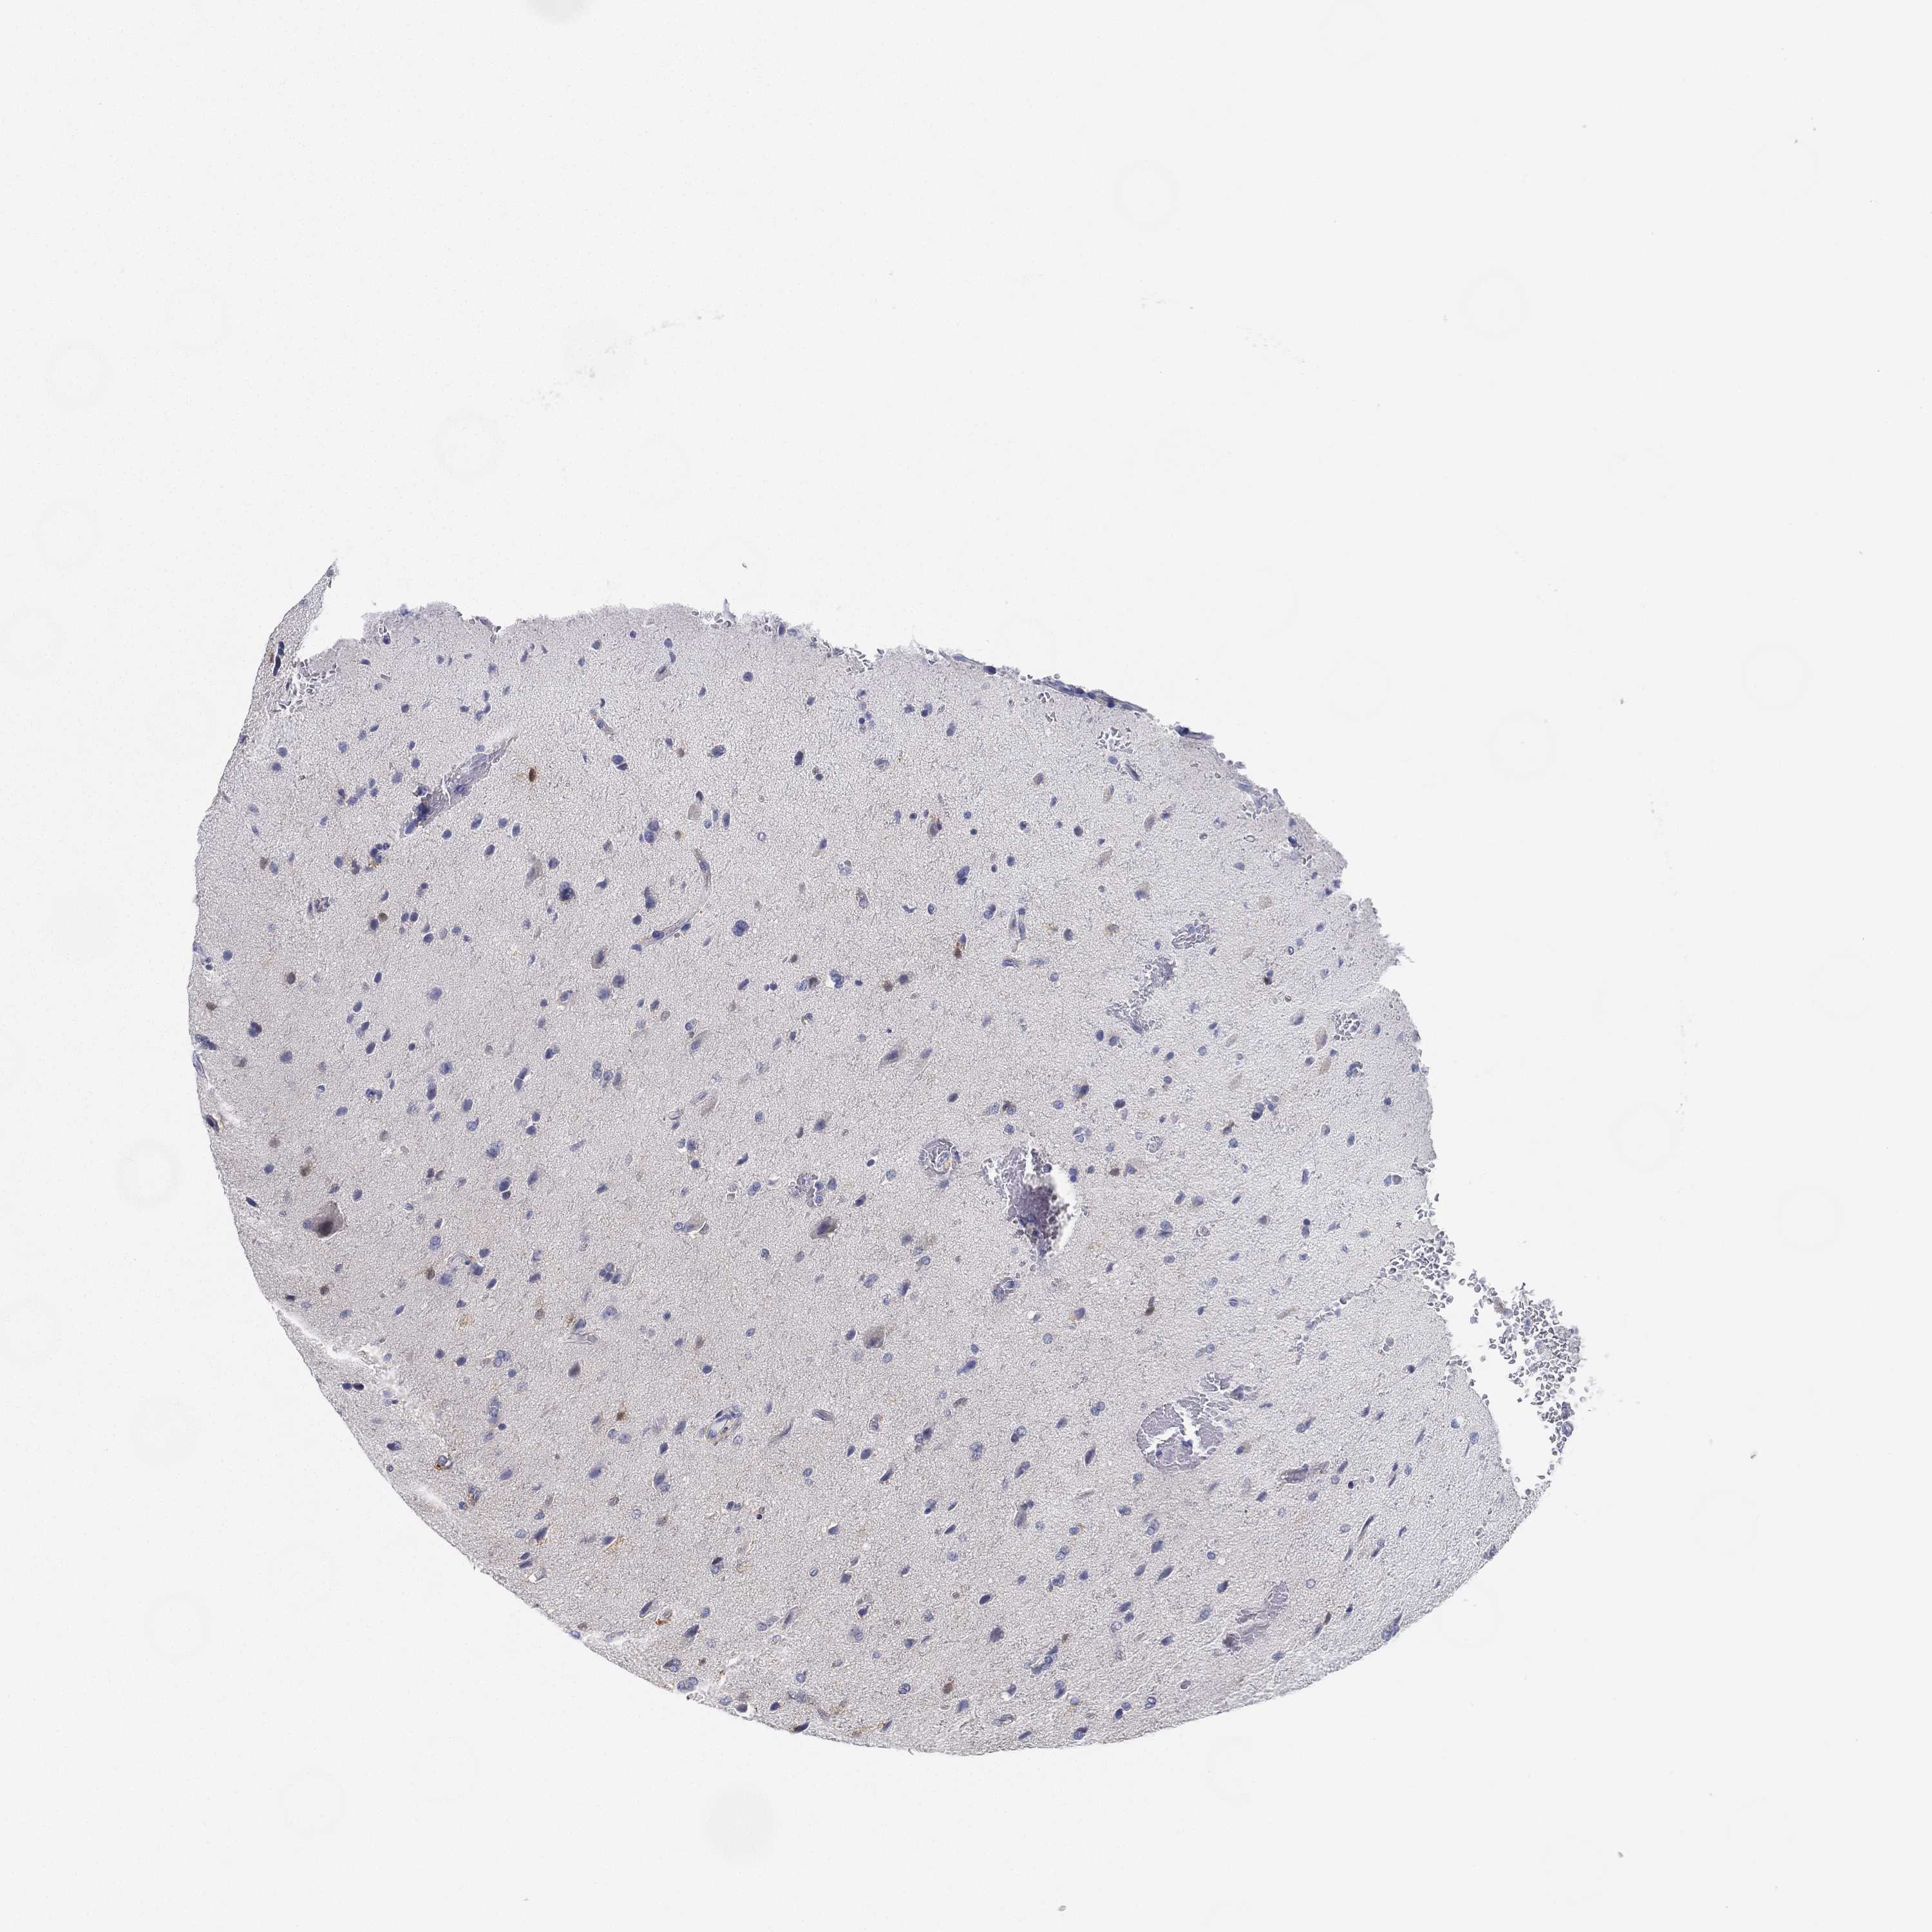

GLIOMA - Protein expressioni

A mouse-over function shows sample information and annotation data. Click on an image to view it in a full screen mode. Samples can be filtered based on level of antibody staining by selecting one or several of the following categories: high, medium, low and not detected. The assay and annotation is described here.

Note that samples used for immunohistochemistry by the Human Protein Atlas do not correspond to samples in the TCGA dataset.

Antibody stainingi

Antibody staining in the annotated cell types in the current human tissue is reported as not detected, low, medium, or high, based on conventional immunohistochemistry profiling in selected tissues. This score is based on the combination of the staining intensity and fraction of stained cells.

Each image is clickable and will lead to virtual microscopy that enables deeper exploration of all samples and also displays staining intensity scores, fraction scores and subcellular localization as well as patient and tissue information for each sample.

Antibody HPA007326

Antibody HPA026088

Glioma, malignant, Low grade

Glioma, malignant, High grade